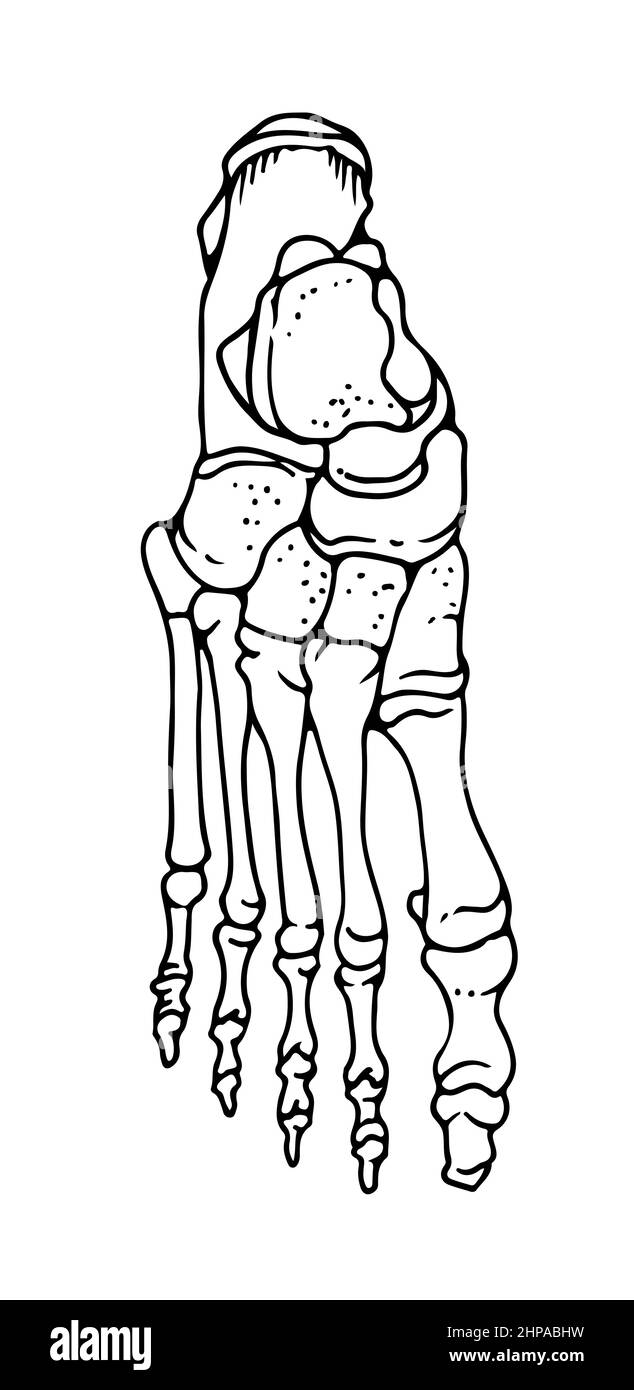

RF2HPABHW–OS du pied humain, illustration vectorielle dessinée à la main isolée sur fond blanc, esquisse anatomique en médecine orthopédique